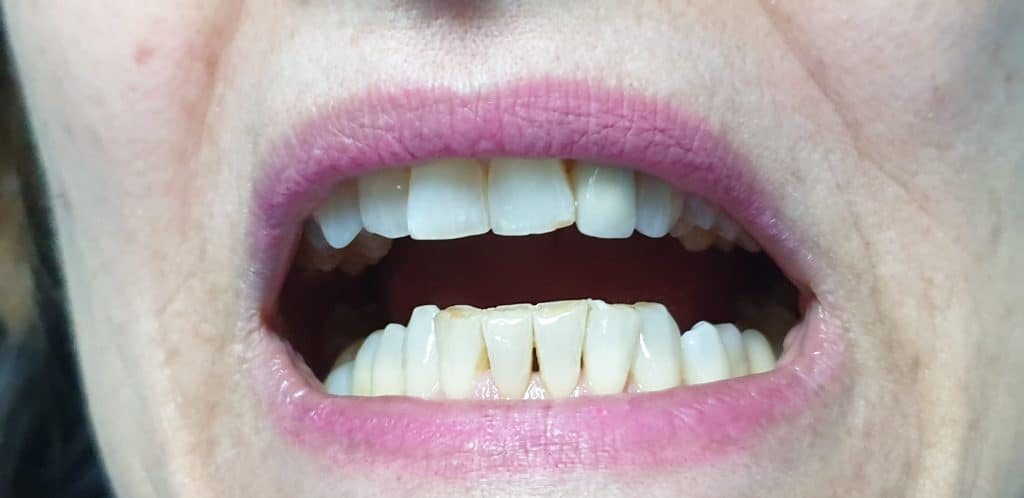

A guarigione avvenuta, si è provveduto a completare il lavoro, inserendo una corona in ceramica.